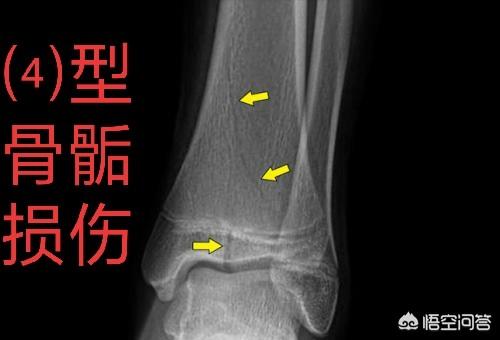

但孩子骨骺损伤会发生的风险并不是骨不愈合或者延迟愈合,而是骨骺早闭,骨桥形成,导致该骨骼部分不生长或者完全不生长,还有就是复位不好,引起的畸形愈合或者短缩愈合。那么相对于对侧健康肢体来说,这条腿变短了或者长歪了。

如果是骨桥形成则在1年左右,骨桥成熟后,手术治疗,切除骨桥矫正。